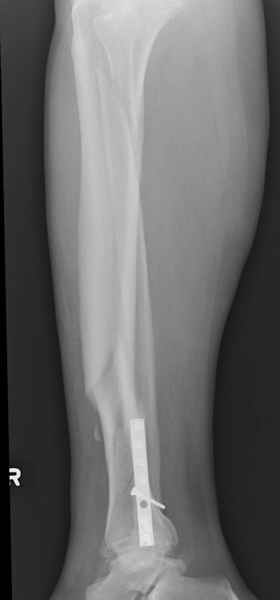

У меня молодой врач на линии, снимки отправил через эл. почту,

спрашивает что делать с больным который поступил недавно, фермер 55 лет падение при пьяной драке в баре, года два назад перенес операцию на лодыжке, на снимках и КТ перелом без вовлечения сустава,

Повреждение такой локализации, на которой применимы и аппарат (классический Илизарова или гибридный), пластина, особенно Locked Plate, и гвоздь с блокированием. В нашей клинике был бы выполнен закрытый интрамедуллярный остеосинтез. Желательно использовать гвоздь с возможностью провести более чем 2 обычных фронтальных винта в дистальном отломке.